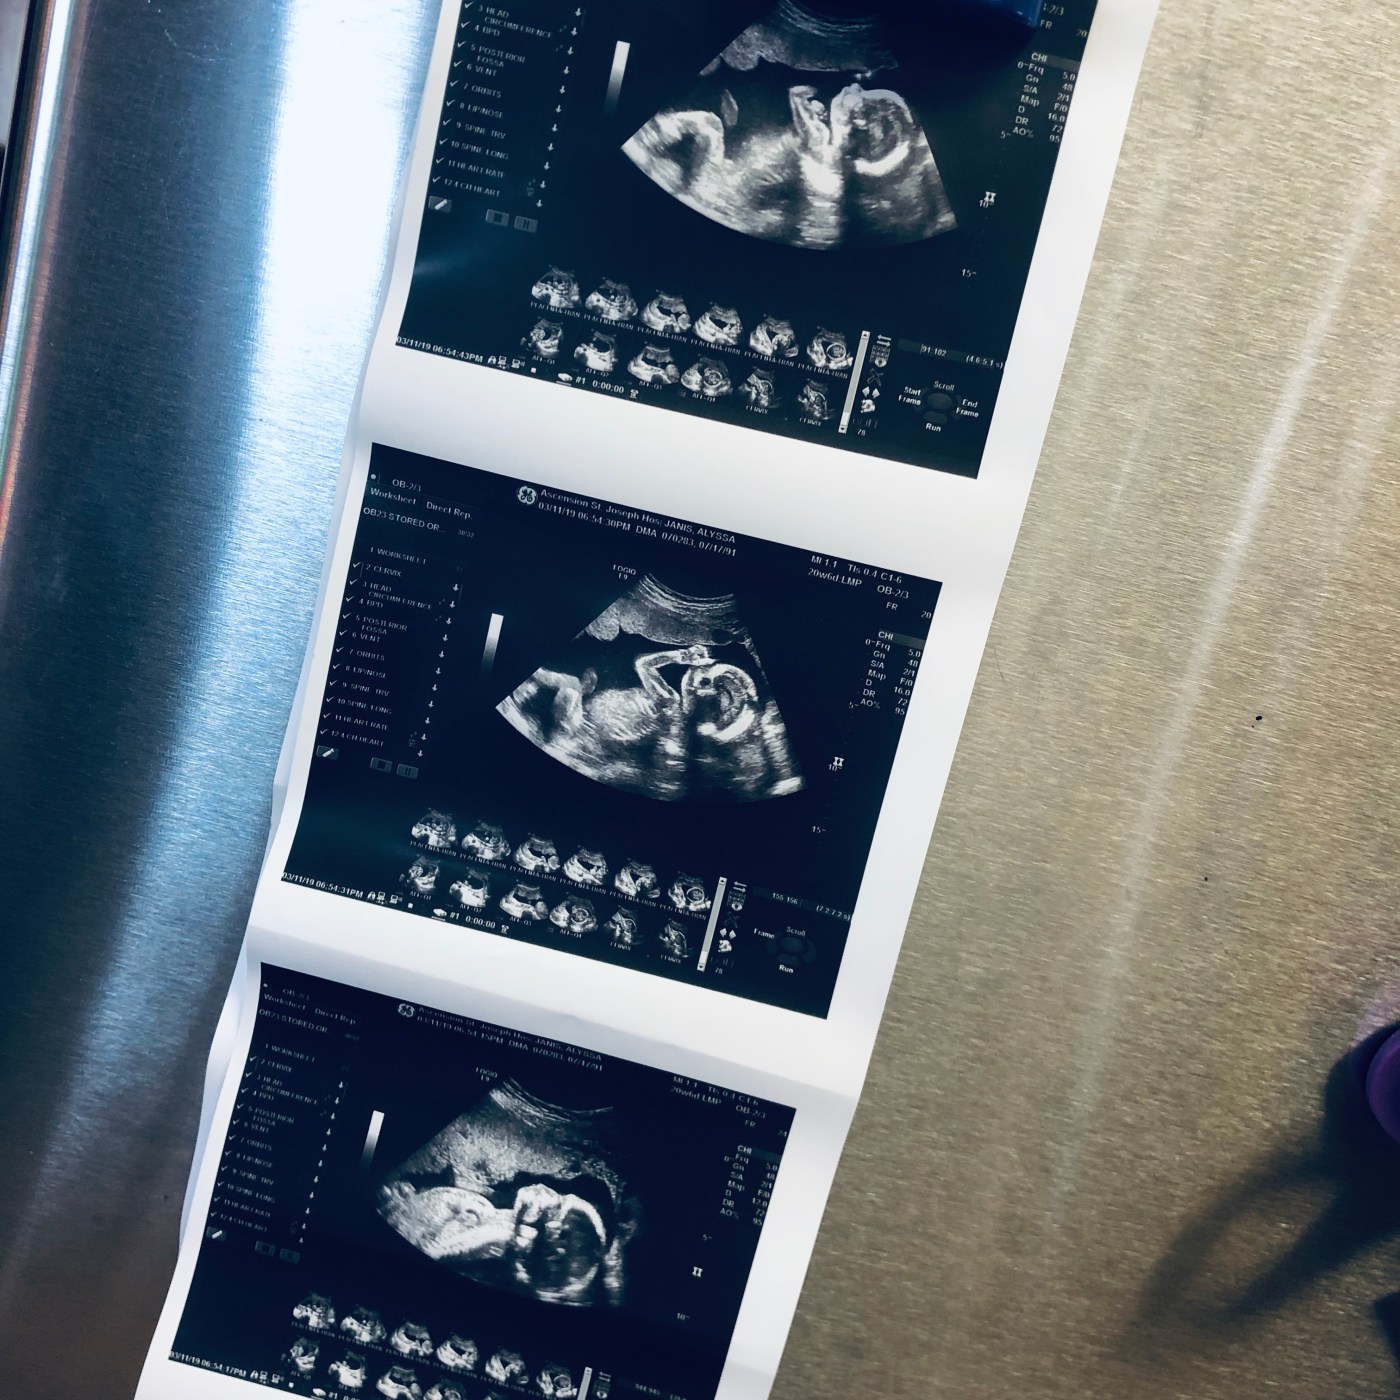

March 11, 2019

7:00am: IT’S ULTRASOUND DAY!!!! We finally get to see our little baby again, and I have been praying and talking with God about calming my nerves for the past week. I am beyond excited to see the baby again, but also so nervous. This is a big day, and I have been feeling more and more peace the more I pray. It is all in God’s hands and I fully trust in him! Our ultrasound isn’t until 6:30pm tonight, so it’ll be a long day of waiting around.

8:30pm: We saw a healthy baby tonight! A healthy baby with functioning organs, beautiful bones, and an adorable little wiggle the whole time we were watching. I actually liked waiting until that time to have my ultrasound because lately the baby has been more active in the evening and we really got to see him or her move! We had the ultrasound technician put the gender of our baby in an envelope so we could save it for our gender reveal this coming Saturday. God is SO good and it was amazing to see our baby tonight. I was all teared up almost throughout the entire ultrasound because I just feel so blessed and thankful that my body has been growing this healthy baby. We are so excited to find out what we are having this weekend!